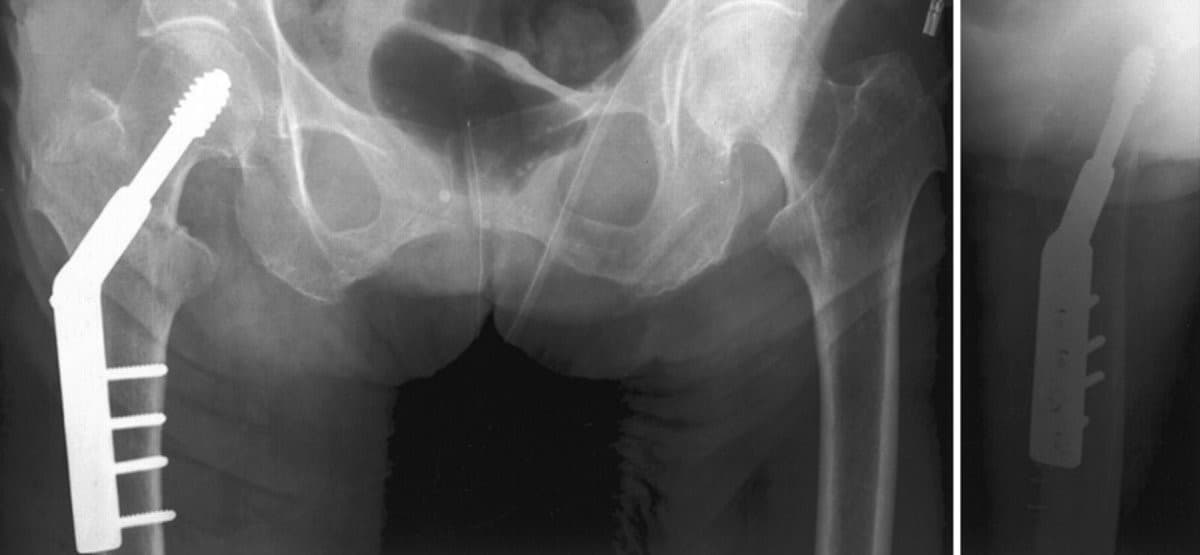

DHS - Дунд чөмөгний гадна бэхэлгээ

Хугарал засах мэс засал image5

УНТЭ-т хийгдсэн мэс заслын зураг

Hip screw-Түнхний шураг

Хугарал засах мэс засал image6